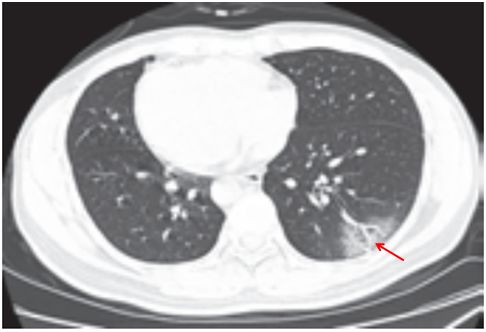

(二)隐球菌感染

肺隐球菌病的病原体为新型隐球菌,此菌为土壤、牛乳、鸽粪和水果等中的腐生菌,感染途径为吸入性。感染人群多见于 40~60岁的成人,临床症状轻,呈亚急性或慢性感染,可侵犯中枢神经系统,表现为慢性脑膜炎、脑膜脑炎或颅内压增高症状。

影像学表现:

(1)呈单发或多发斑片 、 类 圆形 或结 节 影, 多位 于 胸膜下(图 3-11)。

(2)可出现小空洞、晕征,有时呈炎性肿块改变(图 3-12)。

(3)肺门及纵隔淋巴结一般无肿大。

(4)病情进展缓慢。

图片